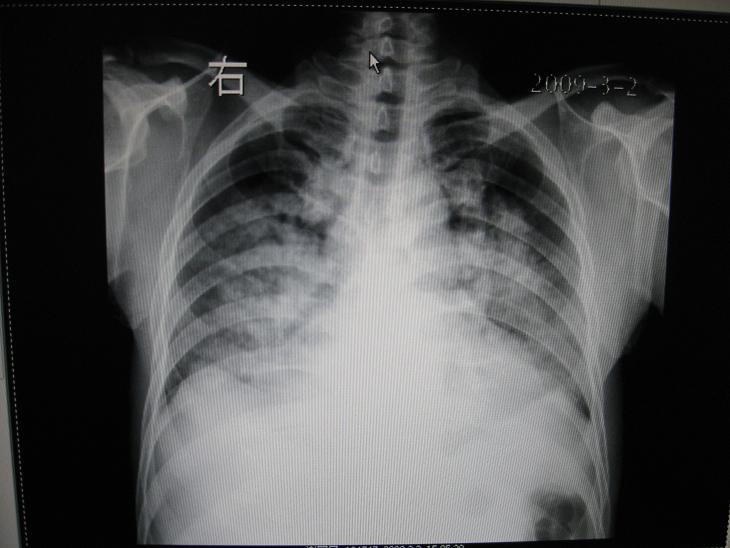

男,36岁,胸闷气喘三天来诊

考虑---肺水肿,双侧胸水。

双肺弥漫性病变 支持肺水肿 双侧胸水

典型肺泡性肺水肿伴双侧胸腔积液。

典型肺泡性肺水肿伴双侧胸腔积液,病因呢?

肺水肿,双侧胸水,不会差,要找以下原因。

支持 1)肺水肿。2)双侧胸腔积液。3)建议进一步检查,并更多的提供病情资料。